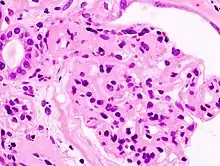

| Microscopic image of diabetic glomerulosclerosis, the main cause of nephrotic syndrome in adults. | |

Secondary causes of nephrotic syndrome have the same histologic patterns as the primary causes, though they may exhibit some differences suggesting a secondary cause, such as inclusion bodies.[24] They are usually described by the underlying cause, such as: